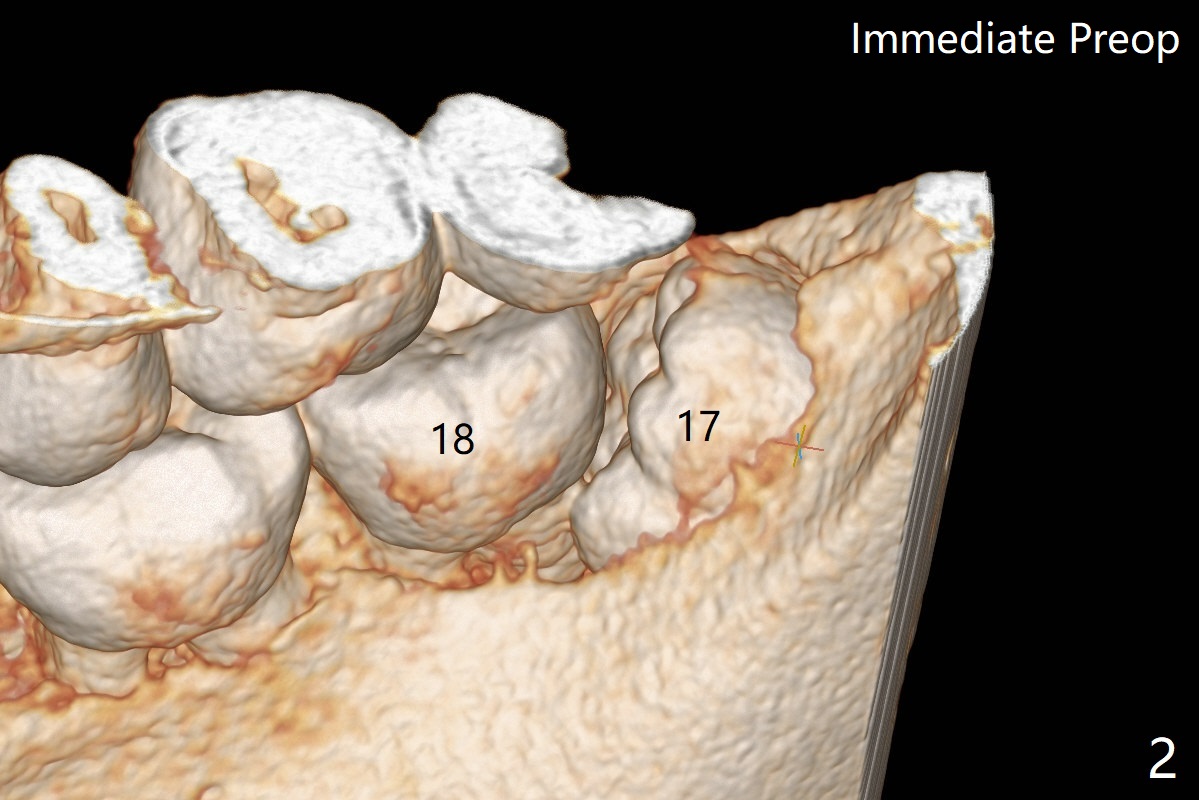

A 35-year-old timid woman finally decides to have 4 of the 3rd molars extracted (Fig.1). The apices of #17 overlaps with the Inferior Alveolar Canal (*). Small field CT shows that #17 is buccal to #18 (Fig.2), causing distal root exposure (Fig.3 D). In fact the buccal overlap seems to be more severe clinically (Fig.4) than what X-ray indicate (Fig.1,3). Therefore bone graft seems to be able to be packed mesially (Fig.5: G). In fact the left Inferior Alveolar Canal is exposed after extraction, collagen plug (P) is placed distal without use of curette around the exposed canal.